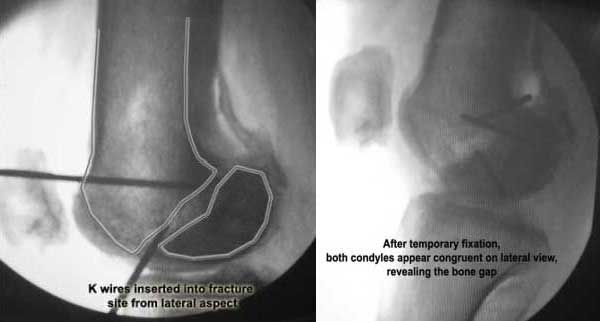

I opened it up from the lateral aspect.

Freed up the non-union site with minimal disturbance to the posterior and lateral soft tissue attachments on the lateral condyle fragment.

Applied a distractor between femoral shaft and tibia, to create a space on the lateral aspect.

This brought the lateral condylar fragment into a position that seemed to be reasonably well aligned, but showed up a bone gap.

Pictures attached.